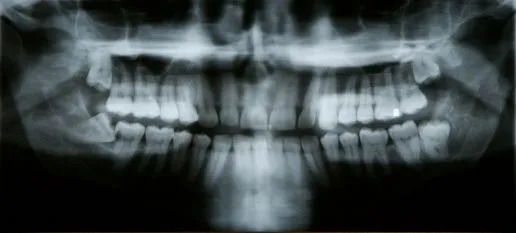

After Impacted Tooth

A tooth becomes impacted when there is not enough room to accommodate the space in the dental arch and growth becomes impossible. After surgery to remove an impacted tooth, mild discomfort and some swelling is expected. This is part of the process and should not alarm you. You may use cold compresses to alleviate the swelling. In addition, your doctor will prescribe pain medication, which should be taken as directed. Patients are also advised to favor the extraction area and modify their diet for a few days to allow for healing.